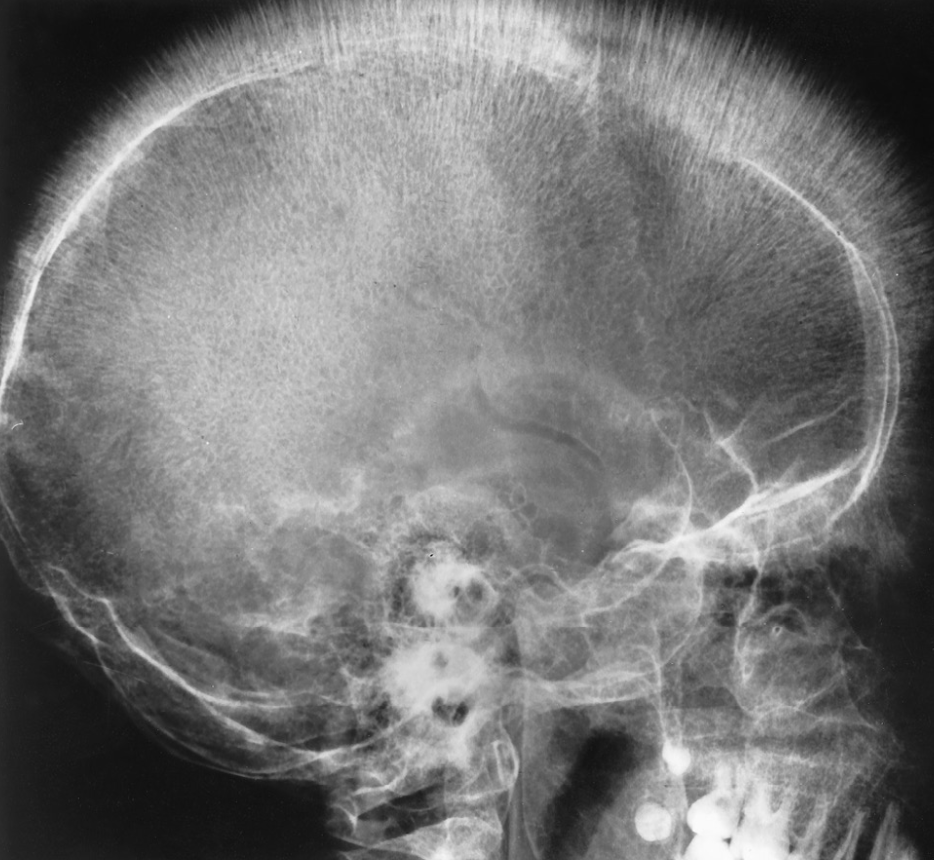

bone thinning

“Hair-on-end appearance” of thalassemia